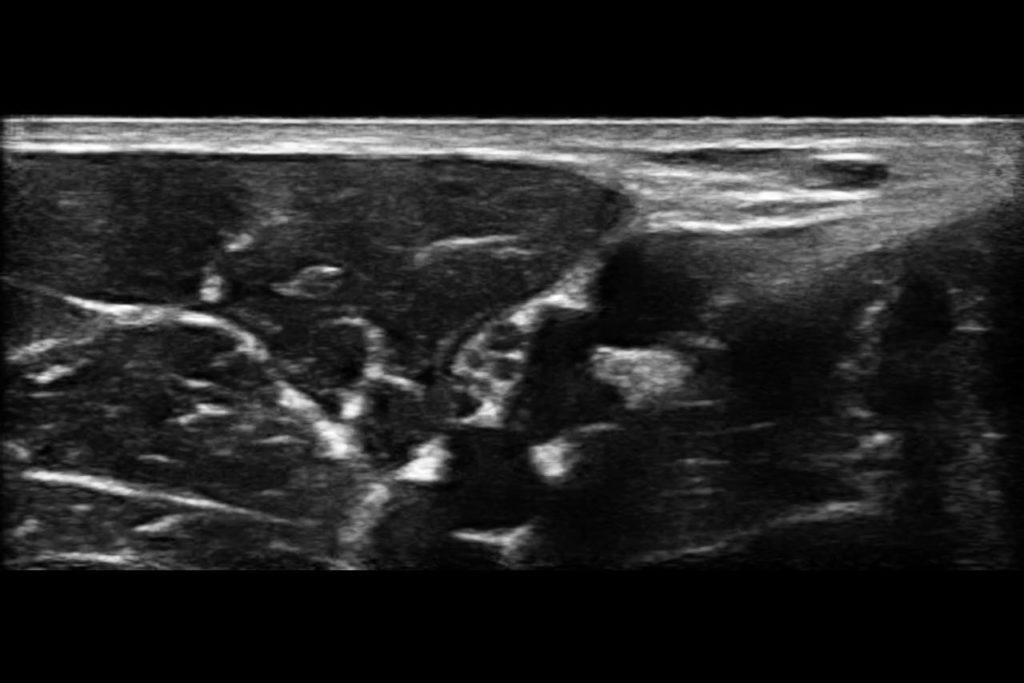

With high-definition imaging comparable to traditional systems, Clarius is the ultimate wireless ultrasound scanner for safe regional nerve blocks and post-operative follow-up.

Now with our wireless Clarius Ultrasound Scanner, we can connect to our iPads and iPhones very easily and take it with us anywhere.